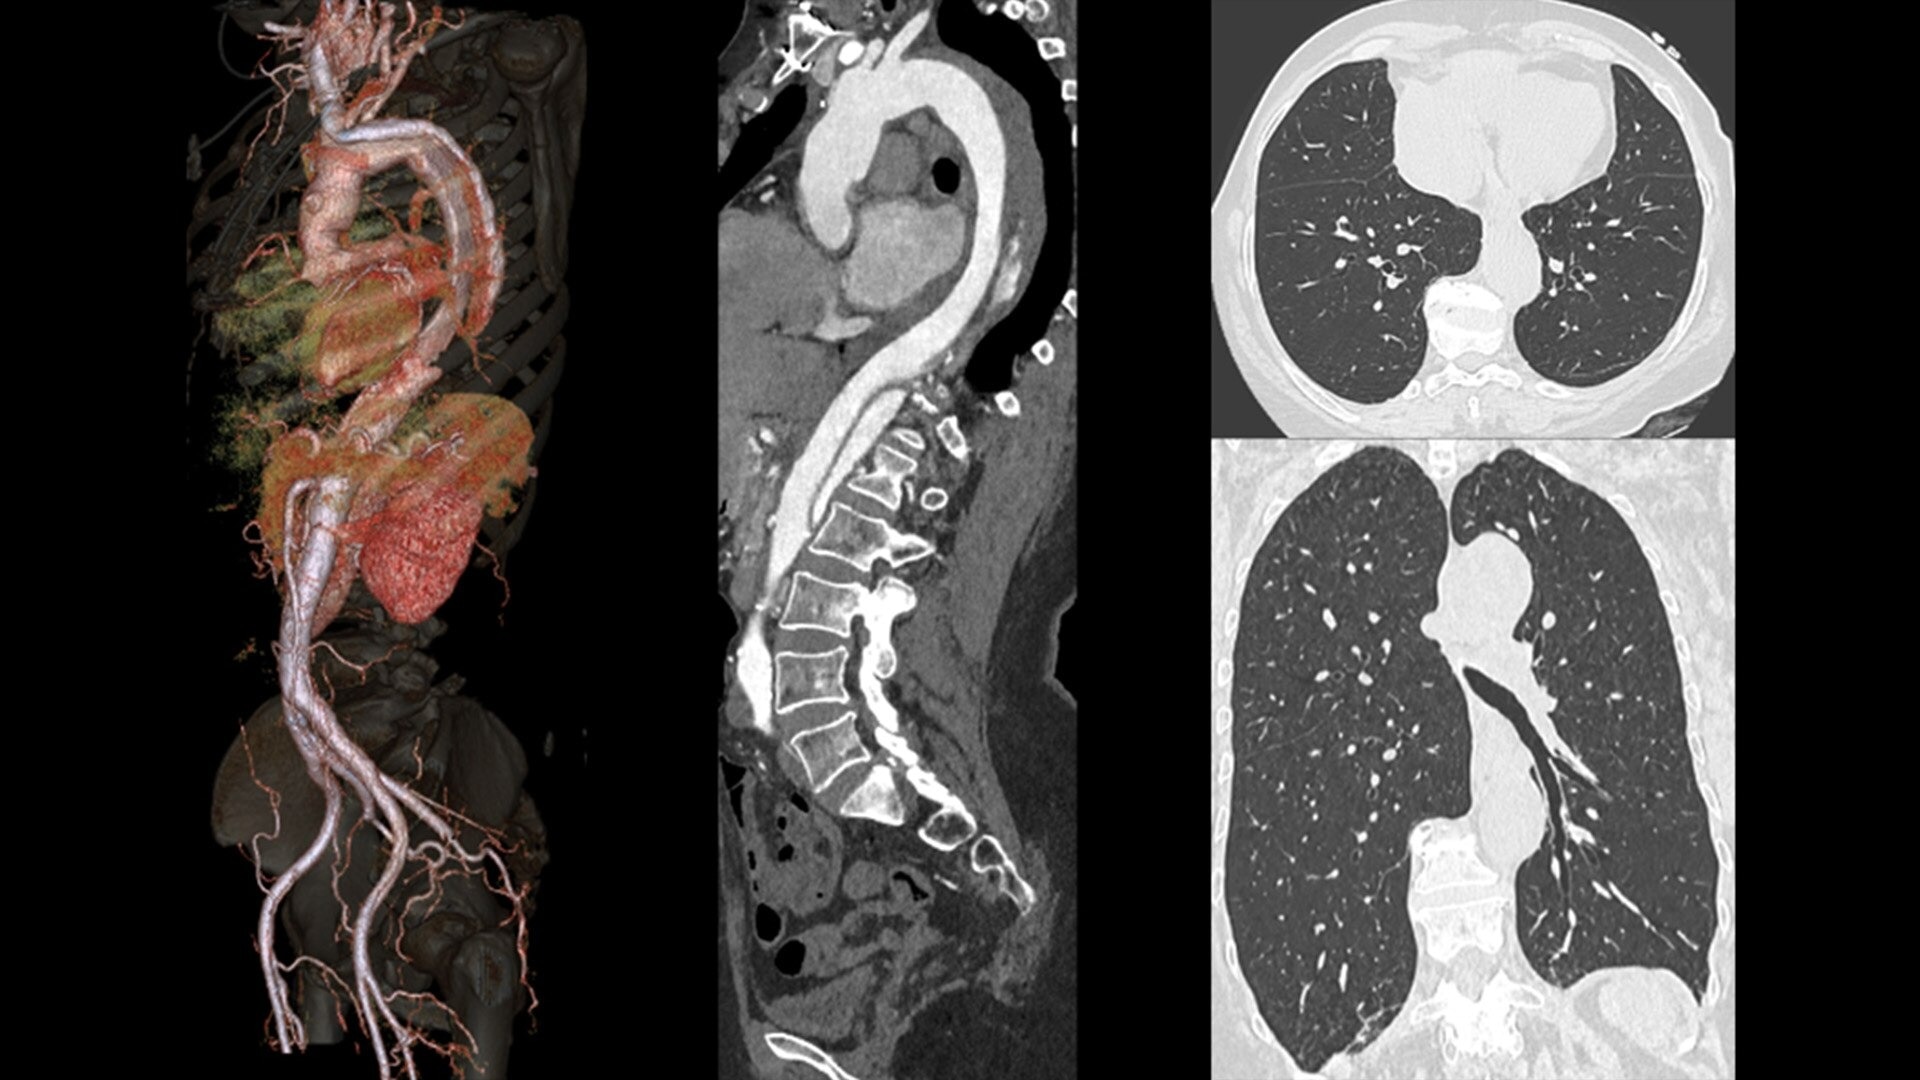

ECG-less Cardiac is a tool that can be utilized in CT examinations where excluding the ECG connection might be desirable, and could help address cardiac exams where patient access and speed need to be prioritized.

These include highly instrumented patients where attaching another ECG device and potentially detaching a diagnostic ECG monitor is not practical. Emergency patients who need access to cardiac evaluation and require fast loading/unloading. In circumstances that prevent obtaining an adequate ECG signal from the patient, and in structural heart assessments.